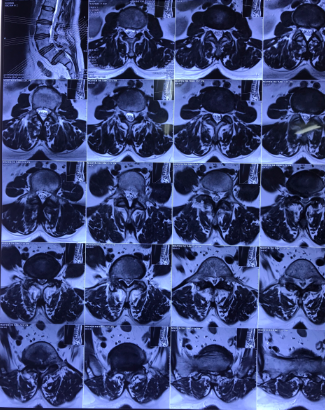

Hình ảnh: Hình ảnh 3D phẫu thuật TLIF

Cho tới nay, phương pháp phẫu thuật nắn chỉnh trượt, cố định cột sống bằng nẹp vít qua cuống, ghép xương liên thân đốt lối sau (sử dung Cage) được cho là hiệu quả nhất, áp dụng phổ biến nhất để điều trị trượt đốt sống thắt lưng.